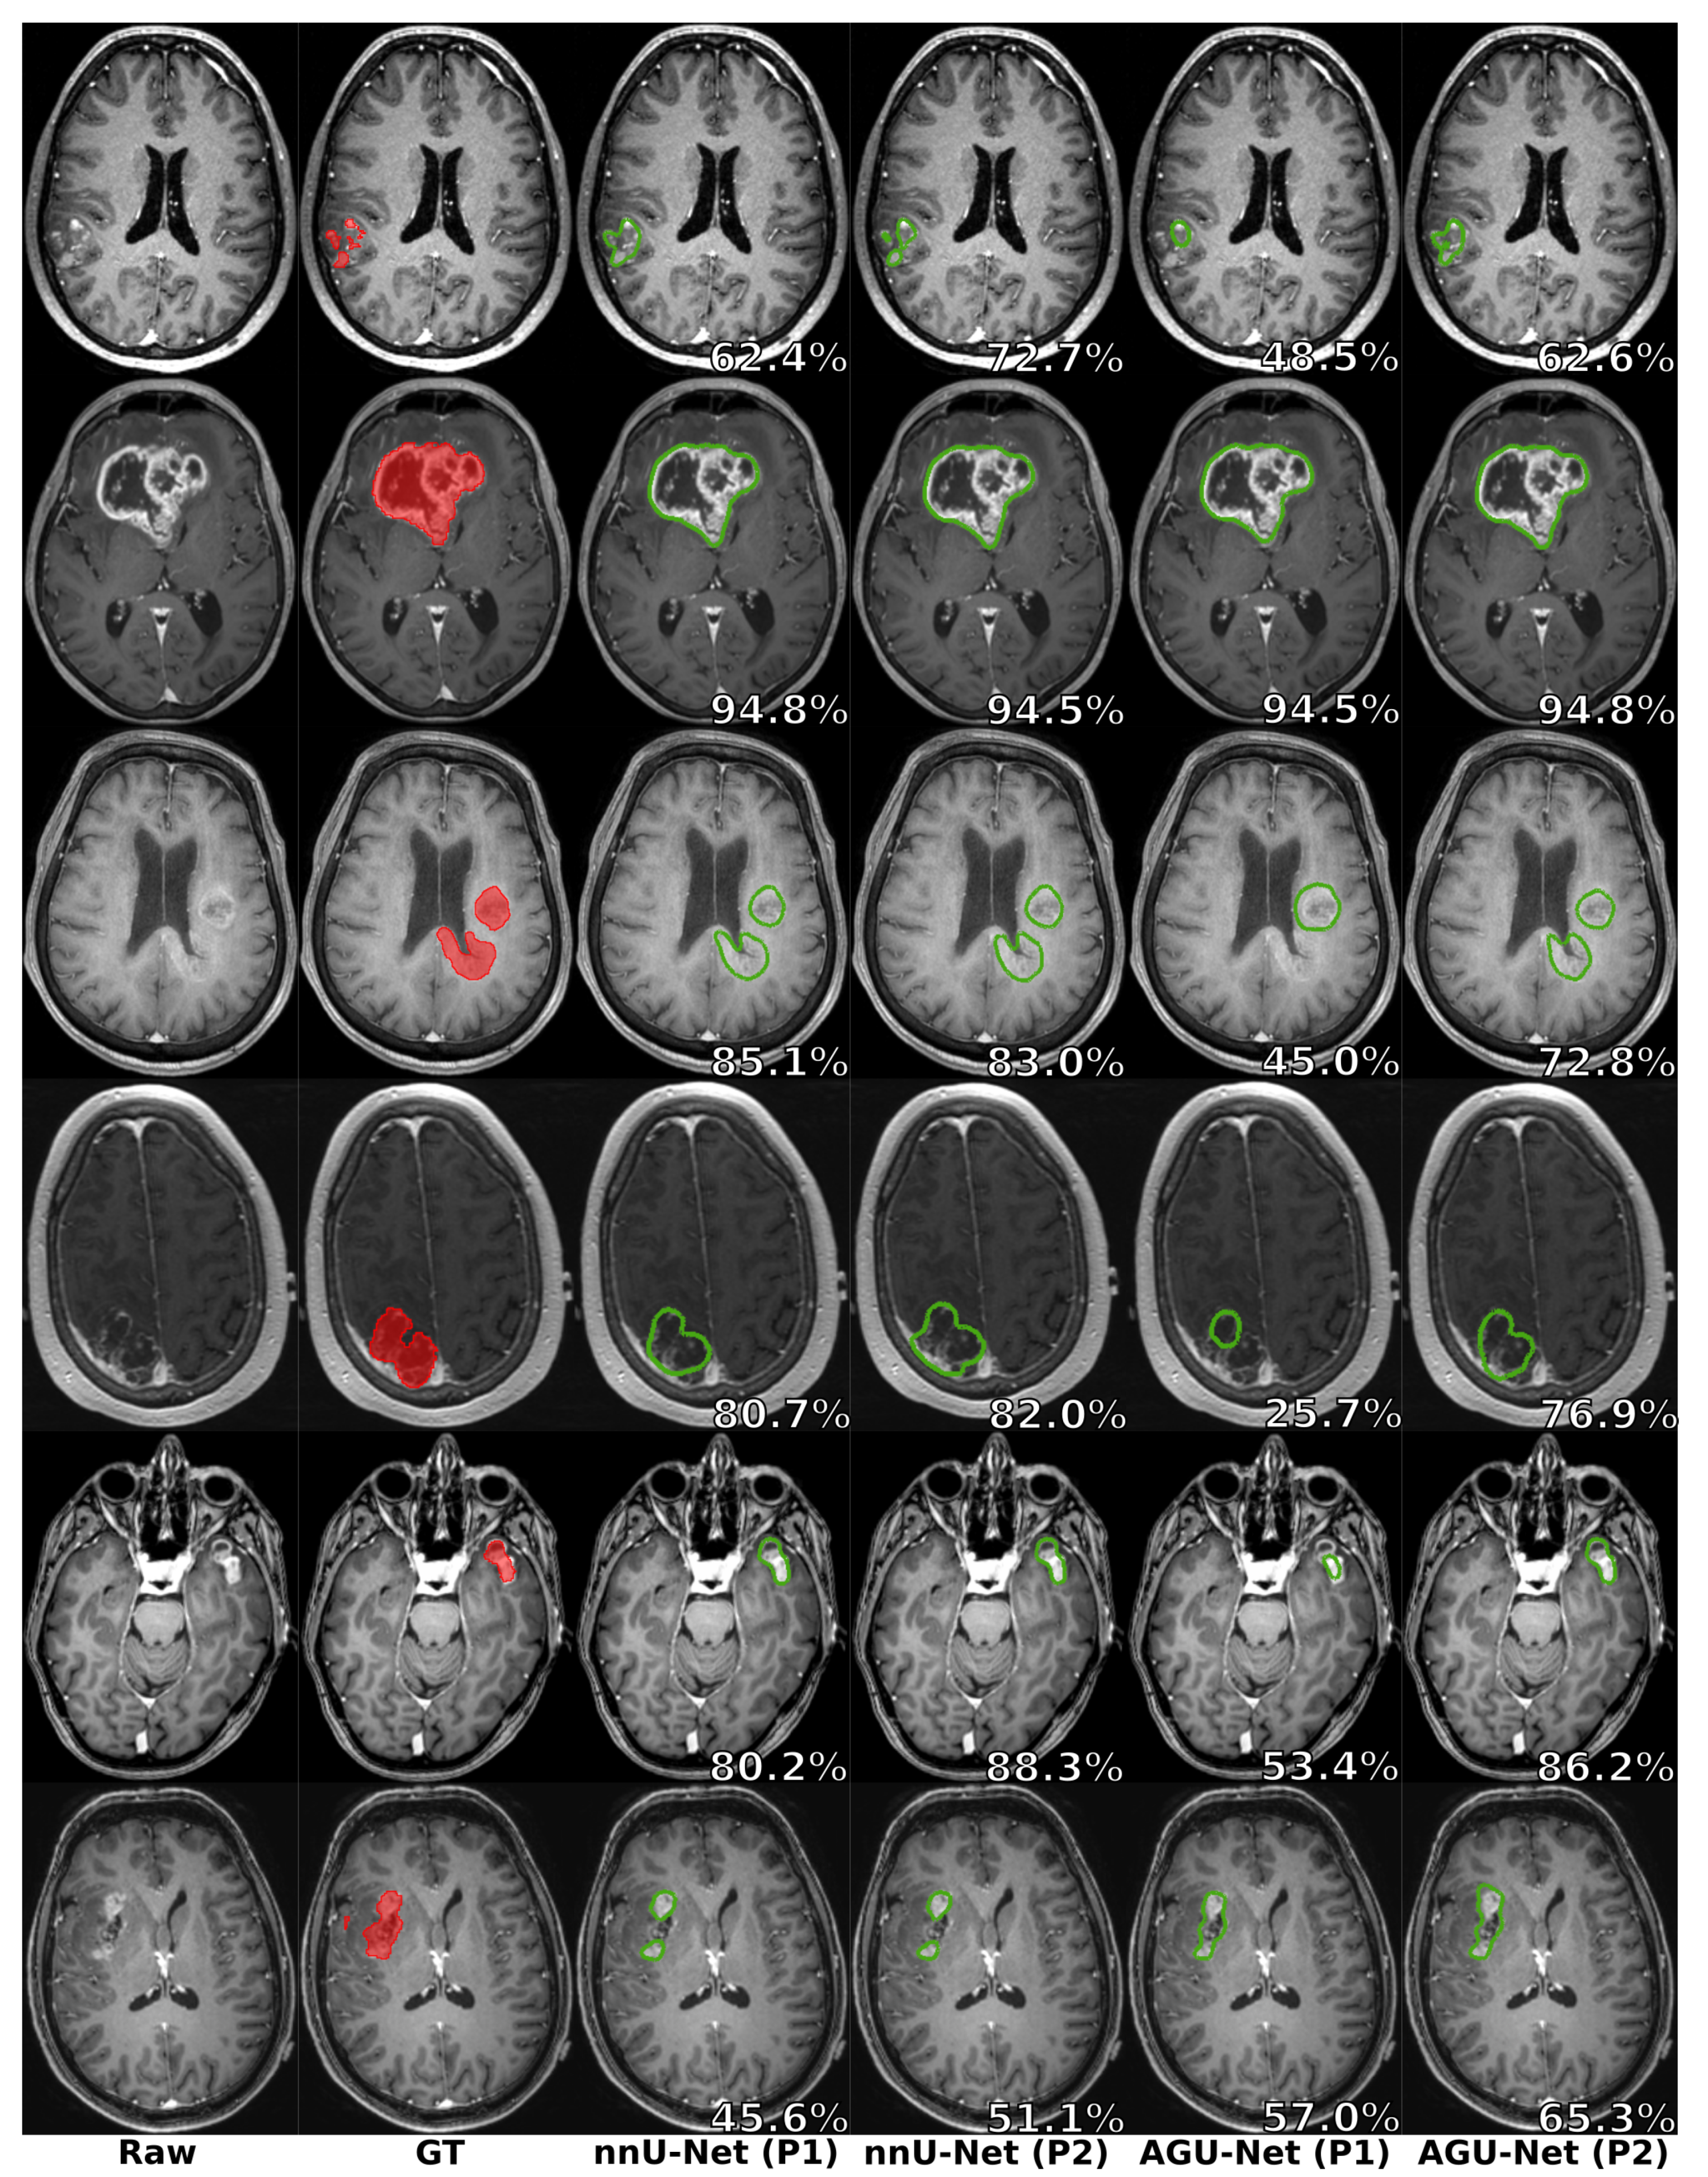

5.4. Preprocessing Impact